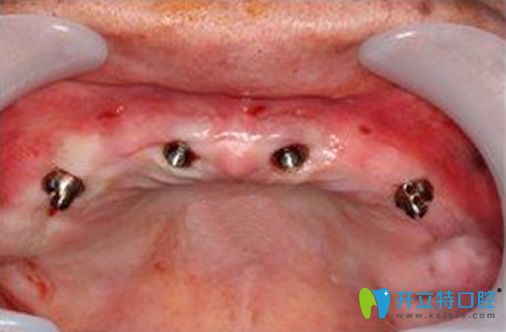

由于王大媽牙齦炎癥比較嚴(yán)重,只能先消炎再做治療啦!隔了幾天黃院長(zhǎng)以非主流的種植牙技術(shù)為王大媽種了4顆種植體。防止牙槽骨吸收,精準(zhǔn)植入效果自然,基臺(tái)密封牢固,修復(fù)了牙齒的靈活性,并且還帶了牙冠。當(dāng)天完成手術(shù)全過(guò)程,解決了食不甘味的痛苦。